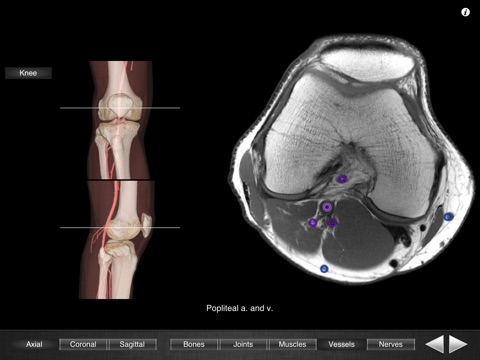

Monster Anatomy - Knee is the free version of Monster Anatomy - Lower limb, an interactive lower limb radiology atlas presented at the 2009 Radiological Society of North America annual meeting. It only contains knee images. The application was developed in the Medical Imaging Department of the University Hospital Center of Nancy, France, under the supervision of Professor Alain Blum. This application is designed for healthcare professionals (Radiologists, General Practitioners, Orthopedists, Surgeons, Physiotherapists among others) as well for students, as a reference and learning tool. It contains 82 contiguous knee MR slices (4-5 mm thickness) in the three anatomical planes. Features: - Intuitive navigation with multiple shortcuts. - Fluid display of images in the three anatomical planes. - 3D Image volume (VR) allows precise location of slice position. - Labels in accordance with the “Terminologia Anatomica" and current literature references. - The five different display modes available (bones, joints, muscles, blood vessels and nerves) facilitates label visualization. - High image quality with a zooming tool. Once the application is installed no network connection is necessary. You can download the full version on the AppStore : "Monster Anatomy - Lower limb" Dont hesitate to give some feedback on the application and to rate and comment on the AppStore! NB : Monster Anatomy - Knee is designed for trained healthcare professionals. This application is not intended as a substitute of patient/healthcare provider interaction or as a replacement of professional judgment.